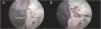

ResultsAfter careful removal of the intraorbital fat, all the extraocular muscles were exposed and dissected, as well as the optic nerve, the ophthalmic artery, and the lacrimal gland. Special emphasis was given to dissecting the nerves’ course from the cavernous sinus to their muscle innervation: Oculomotor and its branches, trochlear, abducent and ophthalmic nerve with its branches (frontal, nasociliary and lacrimal nerve). Each of the 2endoscopic pathways provided a different perspective of the orbit and its structures. After both corridors were completed, a communication between the surgical pathways was highlighted, in a so-called connection area.

ConclusionsThe combination of the EEA and ETOA provides a 360° view of the orbit and its contents. The EEA offers an inferior and medial view of the orbit, through the lamina papyracea of the ethmoid in the first case and through the roof of the maxillary sinus in the latter. At the same time, the ETOA shows a lateral perspective, removing the lateral rim of the orbit, allowing great maneuverability inside the orbit and a wide visualization. This study provides a detailed overview of the surgical neuroanatomy of the orbit, which is an essential and didactic baseline in preparation for practical clinical applications. Overall, EEA and ETOA seem adequate to gain optimal exposure of the orbit and can be adapted to treat a wide range of pathologies. Yet, surgical case series are necessary to establish the true clinical value of these endoscopic approaches in orbital and peri-orbital surgery. However, the limited number of specimens analyzed (5 cadavers, 10 sides) must be acknowledged as a limitation.